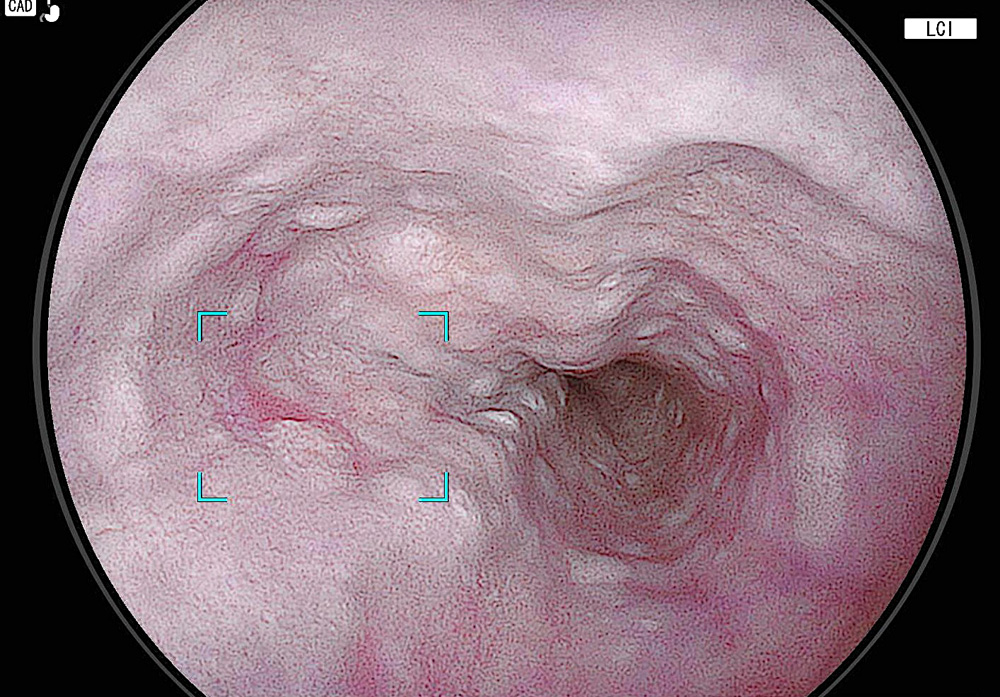

先述のように近年の内視鏡装置はAIによる画像解析をはじめ高解像度カメラが導入され、モニター画面も高精細になっている。これを用いた検査では大腸にできた良性のポリープは、いぼ状になっているので見つけやすいが、早期の食道がんはわずかに赤みを帯びているのみで最新の装置でも炎症か、がんかを見分けることは容易ではない。

その理由について田沼医師は、「食道がんの発見をサポートするAIもありますが、炎症との鑑別が難しいため大腸ポリープより発見が難しい。医師はAIが反応したものが、本当にがんか否かを見分ける力が必要です。AIはあくまでサポートツールであり、うまく使いこなせるかどうかは使用者次第です」と説明する。

「医師は患者さんの飲酒歴などリスクファクターをしっかり調べてから、最新の内視鏡機器を使い病変を早期発見することが必要です。胃カメラ検査でも食道を診ますが、食道上部の下咽頭は耳鼻科の領域にもまたがるので見過ごされることもある。早期発見のためには経験と知識のある専門医に頼るのが一番です」(田沼医師、以下同)